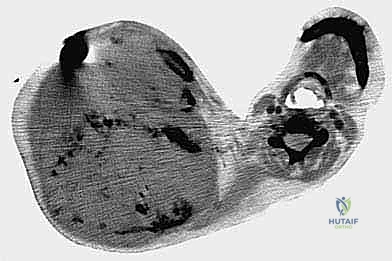

في حالة الأورام الخبيثة (مثل الساركوما)، يمتد الورم غالبًا عبر الحواجز العضلية ويغزو الضفيرة العضدية (شبكة الأعصاب التي تغذي الذراع) والأوعية الدموية تحت الترقوة. لضمان عدم ترك أي خلايا سرطانية (تحقيق هوامش جراحية سلبية)، يجب إزالة الكتف بالكامل كوحدة واحدة (En Bloc resection).

- ساركوما العظام (Osteosarcoma & Ewing's Sarcoma): أورام عظمية خبيثة تنشأ في الطرف العلوي لعظمة العضد أو لوح الكتف وتكون قد وصلت لمرحلة متقدمة لا تستجيب للعلاج الكيميائي.

- ساركوما الأنسجة الرخوة (Soft Tissue Sarcoma): أورام ضخمة تنشأ في العضلات أو الأنسجة المحيطة بالكتف وتغزو الأوعية الدموية الرئيسية والأعصاب.

الخطوة 5: تحرير لوح الكتف والطرف (Scapular Mobilization)

ينتقل الجراح إلى الجزء الخلفي. يتم قطع العضلات التي تربط لوح الكتف بالقفص الصدري والعمود الفقري (مثل العضلة شبه المنحرفة، والعضلة الظهرية العريضة، والعضلات المعينية).

الخطوة 6: استئصال الورم والطرف (En Bloc Resection)

بمجرد تحرير جميع التوصيلات العظمية والعضلية والوعائية، يتم إزالة الطرف العلوي بأكمله مع الكتف والورم ككتلة واحدة، دون اختراق كبسولة الورم لضمان عدم تسرب الخلايا السرطانية.